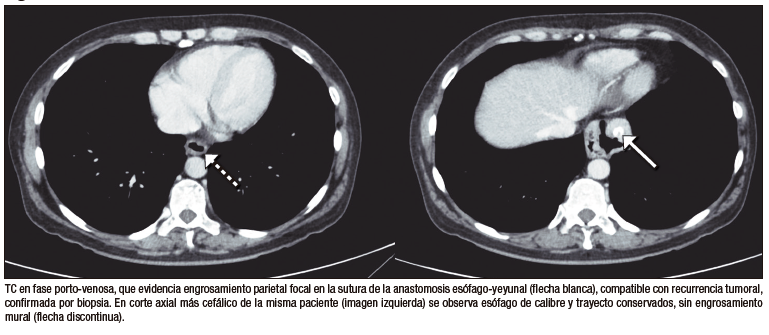

Recidiva neoplásica

● Caso 7. Mujer de 55 años con antecedente de gastrectomía total y linfadenectomía por adenocarcinoma gástrico localmente avanzado, tratada posteriormente con quimioterapia adyuvante. En el seguimiento oncológico, mediante una TC de tórax, abdomen y pelvis, se identificó un engrosamiento parietal focal en la anastomosis esófago-yeyunal. La endoscopía digestiva alta con biopsia confirmó carcinoma in situ. Se decidió manejo paliativo con quimioterapia sistémica.

Entre las complicaciones tardías, la recidiva tumoral en la anastomosis se sospecha en TC por engrosamiento mural focal, siendo el diagnóstico definitivo histológico.12 La úlcera perianastomótica puede manifestarse con abdomen agudo, y en TC se identifica como un defecto focal de la mucosa con burbujas de gas extraluminales.13 La hernia hiatal complicada, en tanto, constituye una causa de obstrucción intestinal diferida; la TC permite evidenciar el ascenso de asas al mediastino y el punto de transición, diferenciándose de otras causas, como bridas o hernias internas.14